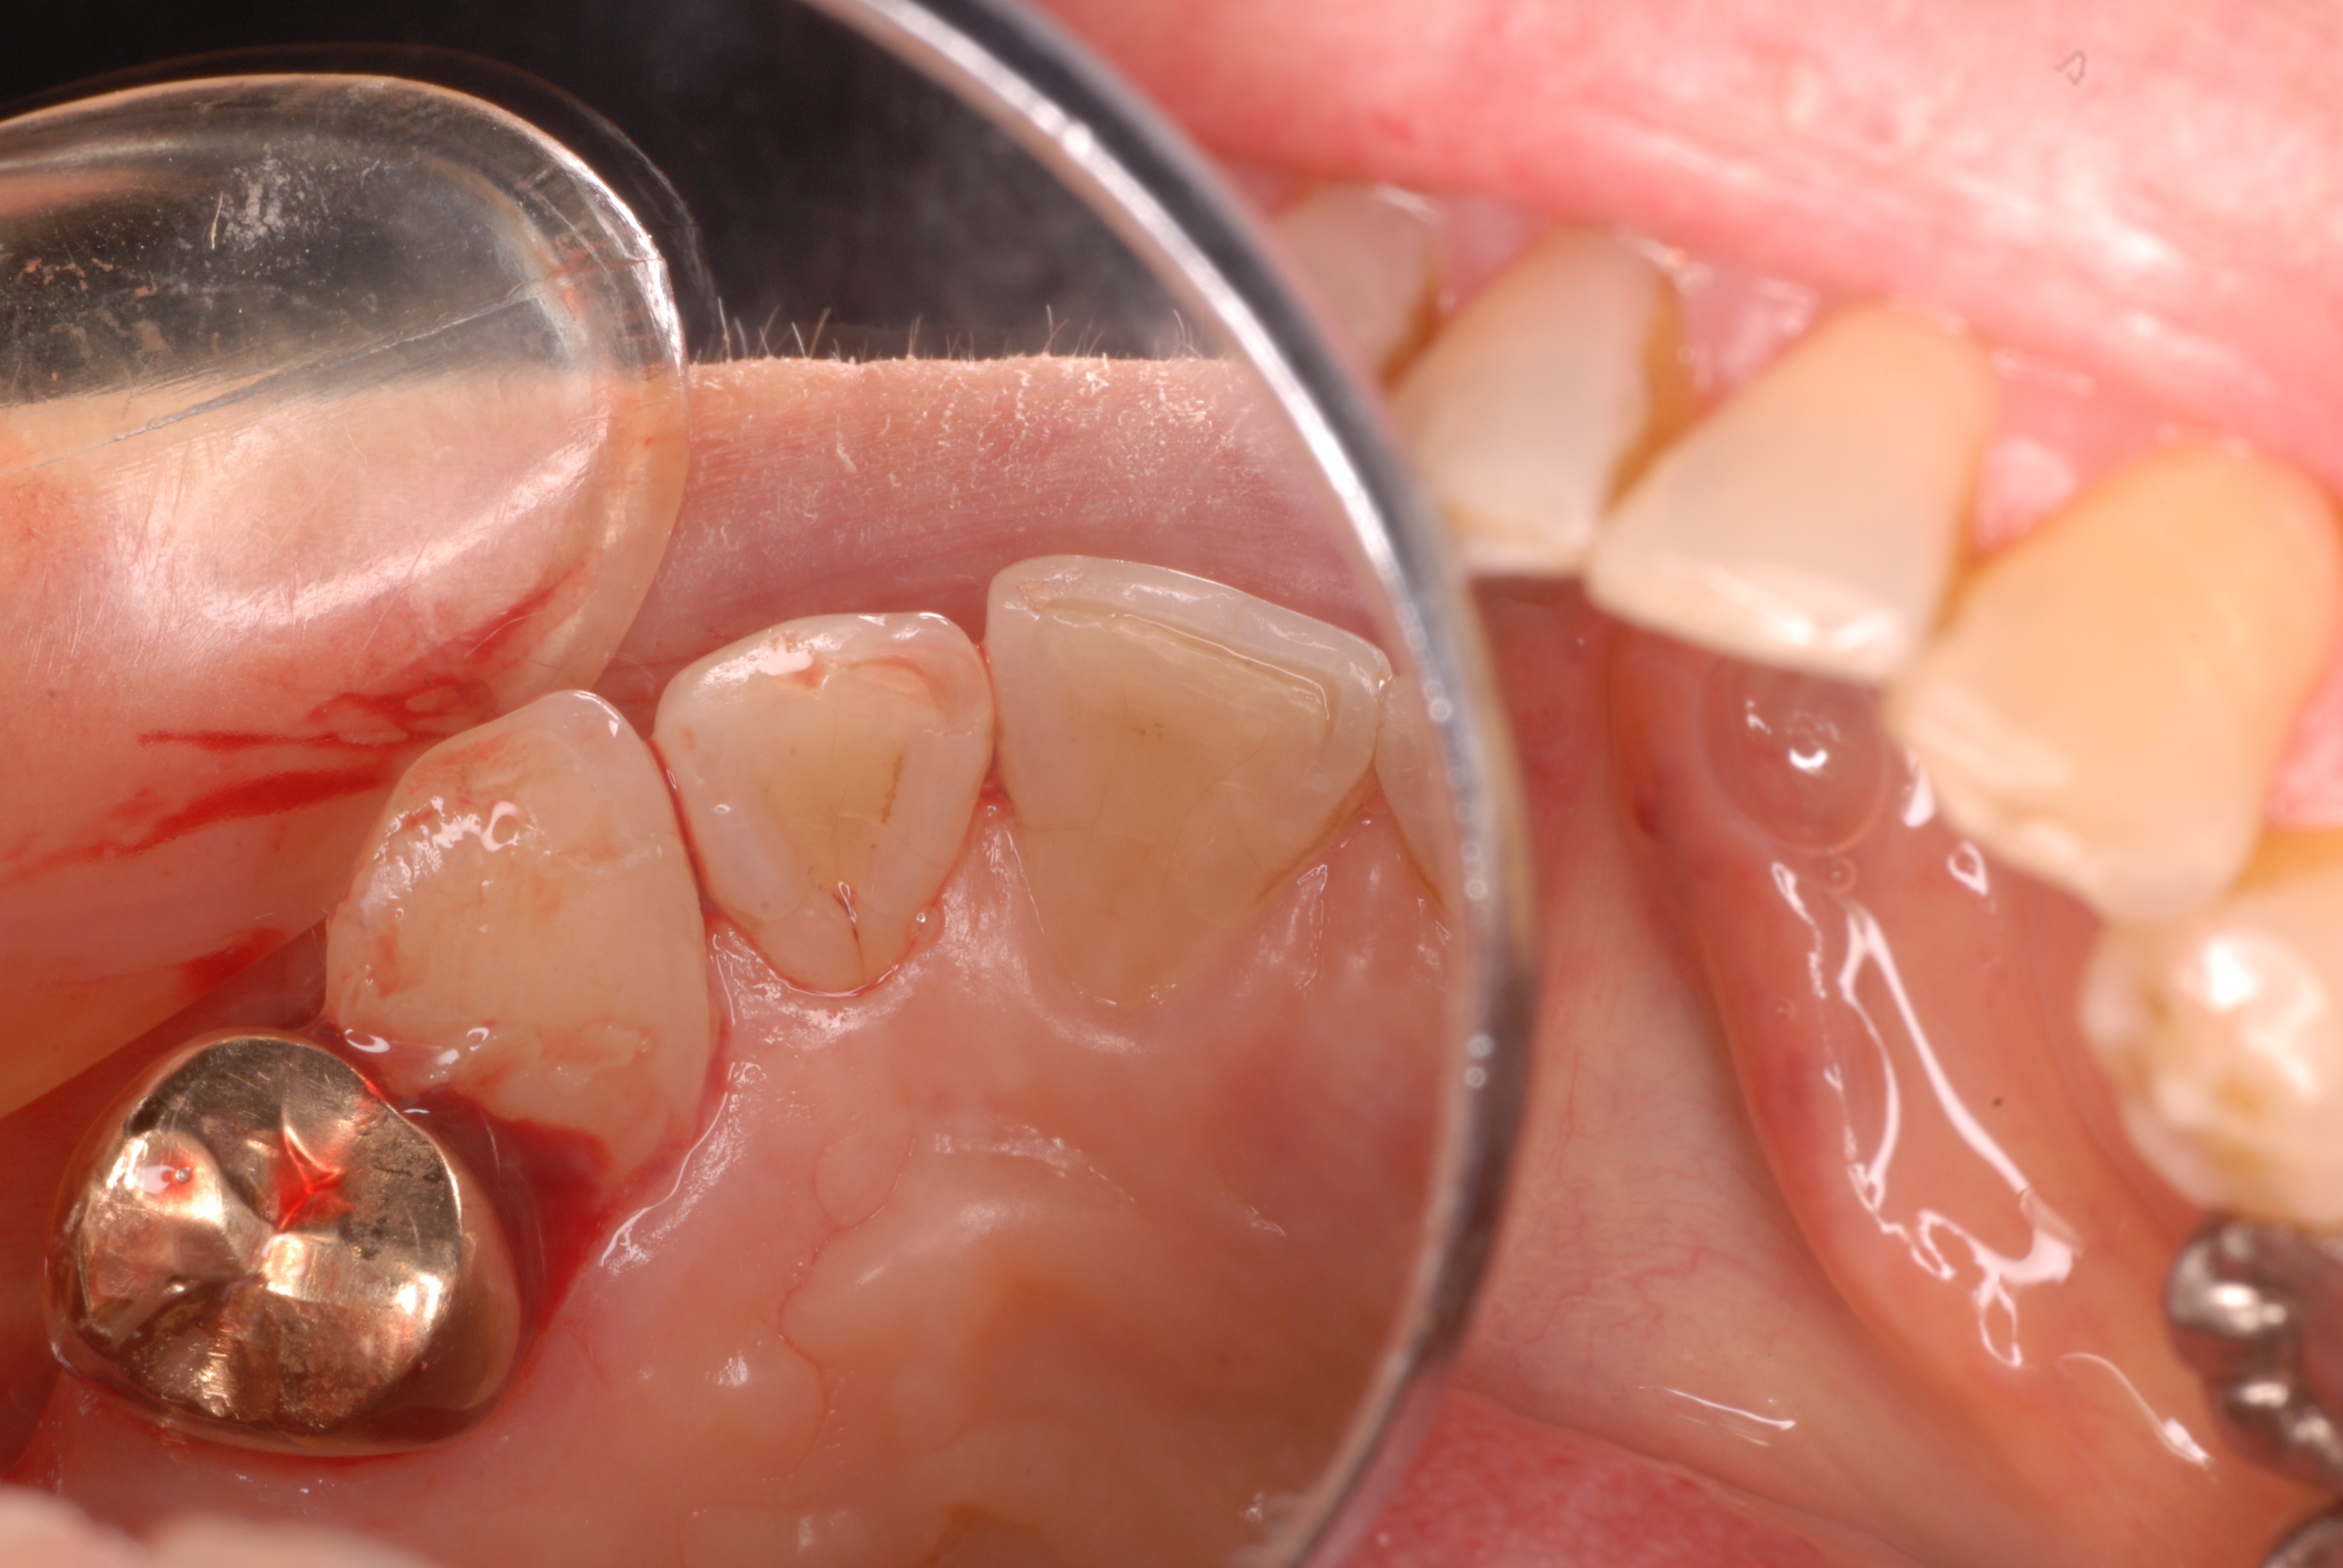

ばい菌が歯の中に侵入しないようにまず歯の形を変えなければならないことがあります。そして形を整えてからラバーダムというゴムなどで隔離してばい菌が侵入しないように、又消毒薬がお口に漏れないようにして歯の中からばい菌の塊である、“虫歯”や“神経”の中に残っている汚染された歯質を除去していかないかぎり、痛みや顎の中の骨の破壊はとめられないのです。

又神経という歯の中の穴は複数あるのですが、拡大鏡で覗かなければ見落としてしまう事も多いのです。

右上に穴が二つ見えますか?一つは以前治療した先生が開けた穴ですが途中で閉塞していまいた。そしてその下に別の神経の穴が存在していたのですが、拡大鏡で見ていないので見えていなかったか注意不足で腐れた神経を取り残して腐敗していました。細いのでわからなかったのかもしれません。

DSC_0048

拡大鏡でみるとはっきりと見えます。同じ場所のようにレントゲンではみえますが全然別の神経の穴だったのです。

DSC_0047

私も最近は必ず拡大鏡で確認してから治療を始めます。

しかし保険の治療費では本当にこだわればこだわるほど“赤字”になります。